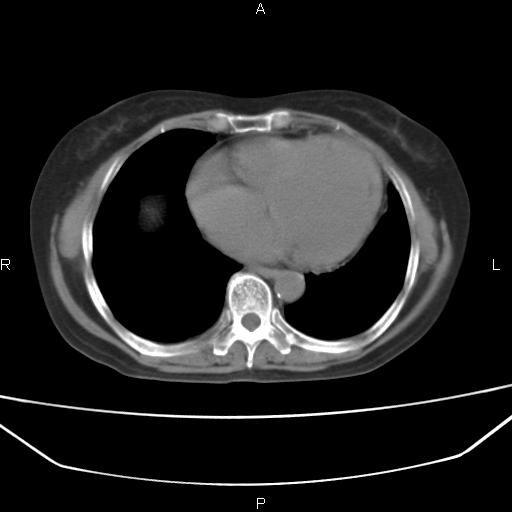

患者,女,66岁。健康体检胸部透视发现右上肺片状阴影。既往无不适,患者自诉三个月前曾有低热病史体温37.5左右一周。用药后缓解。至今无其它不适。请老师们指导指导。

考虑:右肺上叶周围型肺癌(分叶状肿块+砂粒状钙化+胸膜尾征)。

病灶见明显分叶、大小较大(大于3cm?),老年人,多考虑:肺癌,建议穿刺活检。

典型的中心型肺癌,尖段支气管阻塞。

以下是引用dyqct在2010-6-3 9:32:00的发言:[br]考虑:右肺上叶周围型肺癌(分叶状肿块+砂粒状钙化+胸膜尾征)。

不像中央型啊

周围性肺癌,

右肺上叶周围型肺癌可能性大。

考虑:右肺上叶周围型肺癌